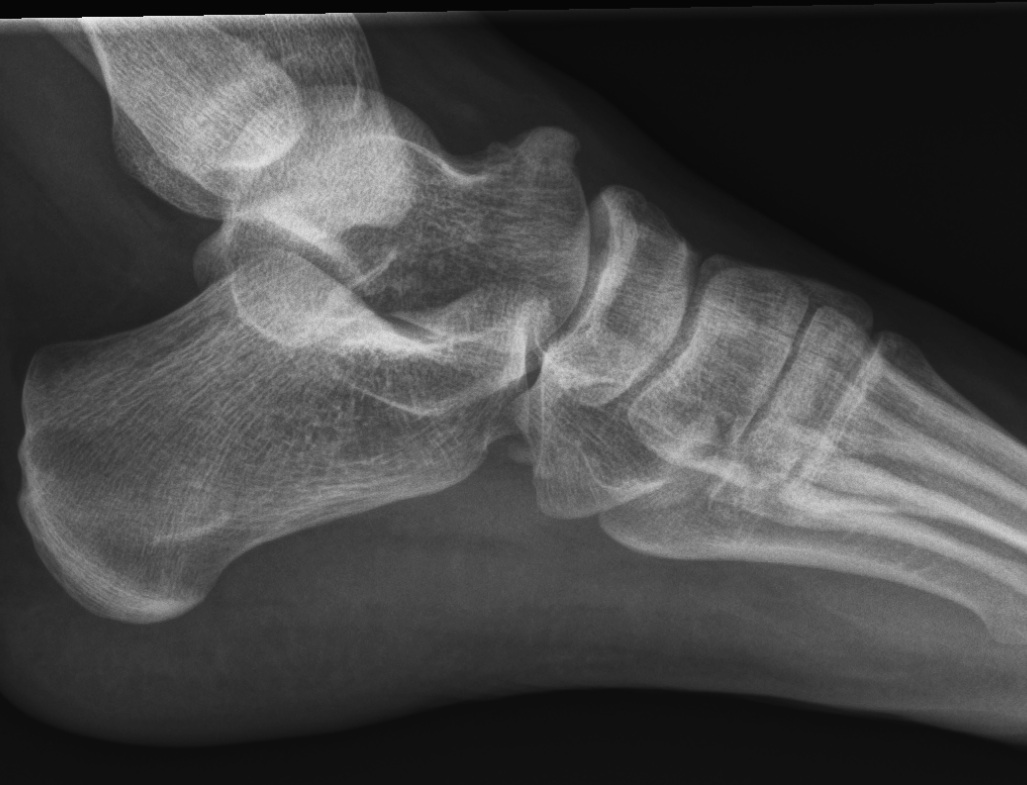

Xray

| Talar beaking | C Sign | Harris axial view | Ball and socket ankle joint |

|---|---|---|---|

| Traction spur due to increased stress | Medial outline talar dome and posterior sustenaculum tali |

40 degree axial view Ski jump view Visualize middle facet |

Secondary to rigid subtalar joint Develops to allow inversion / eversion |

Talar beaking with C sign